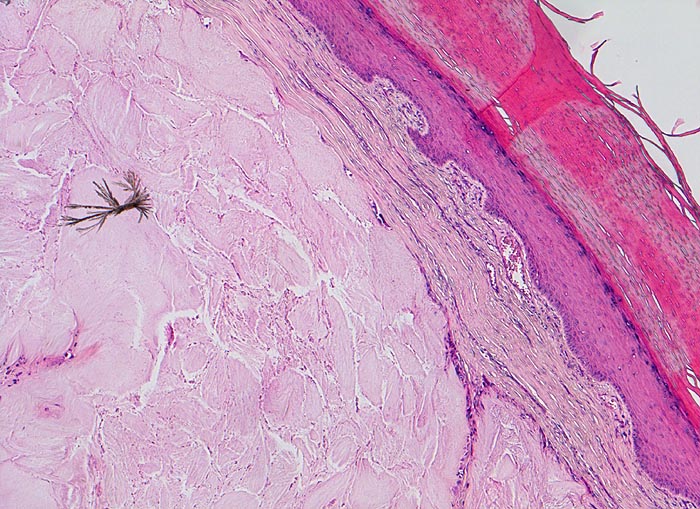

• Kollagenes Bindegewebe mit Tophus bestehend aus wolkiger eosinophiler Matrix mit herdförmig erkennbaren nadelförmigen Strukturen (Uratkristalle).

• Die Ablagerungen sind umgeben von mehrkernigen Fremdkörperriesenzellen, Makrophagen und wenigen neutrophilen Granulozyten.